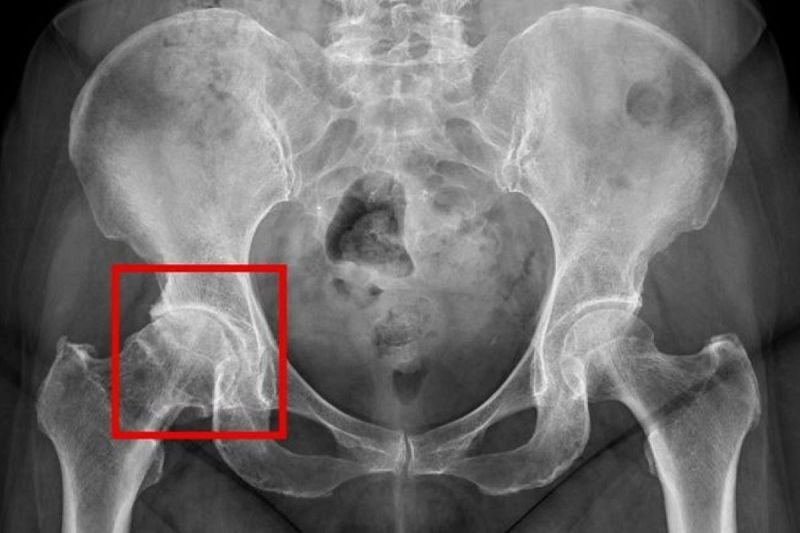

髖關節疼痛初期治療上多採「保守治療」為主,包括休息、使用消炎止痛藥物、熱敷、電療或減重,藉此減輕疼痛、維持關節活動度及延緩退化。針對嚴重髖關節退化的病人,人工髖關節置換手術為主要治療方式,醫師會在術前透過X光等影像檢查,評估關節磨損程度與骨骼狀況,以規劃適合的手術方式。黃振文醫師說明,傳統手術多從髖關節外側或後側進入,需切開部分肌肉組織;而近年發展的「正前開微創手術」,則是將大腿前側切開,從股直肌及闊筋膜張肌的肌肉間隙分開,打開關節囊並移除磨損的骨頭及軟骨組織,再置換人工關節零件。此術式因為從肌肉自然間隙進入,可減少肌肉破壞,降低術後前期的疼痛並加快恢復速度;術後配合復健計畫、遵循醫囑進行活動與保養,有助於提升關節功能與延長人工關節使用年限。但「正前開微創手術」並非適合所有病人,體重過重者較難透過肌肉自然間隙進入,視情況將採取傳統手術;血糖控制不佳者,因容易有術後感染,僅能考慮保守治療、注射治療等非侵入療法。